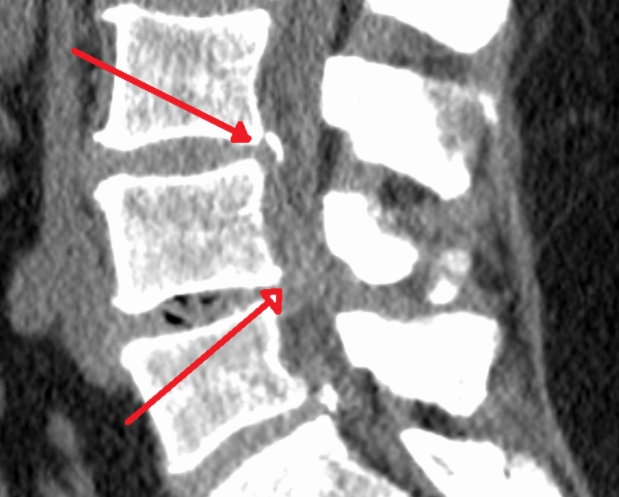

척추는 추골이라 불리는 뼈가 연결되어 이루어져 있습니다. 그런데 나이를 먹으면서 노화와 함께 추골에 있는 척추관이라 불리는 신경이 통과하는 길이 좁아지게 됩니다. 이렇게 좁아지게 되면 그 안을 통과하고 있는 신경이 압박을 받아서 허리통증과 엉덩이, 다리가 저리는 증상 까지도 나타나게 됩니다.

노화 등의 영향으로 추간판이나 요추가 변형 변성되어 척추관이 좁아지면 그 안을 통과하는 마미신경이 압박을 받게 됩니다. 마미신경이란 다리쪽 신경을 조절하는 신경입니다. 그런데 이 부분이 압박을 받으면 신경이 영향을 받아 다리에까지 통증이 나타나고 저리는 등의 척추관 협착증 증상 보이게 됩니다.

척추관 협착증 이란 노화로 인한 변화로 추간판 변성과 뼈 변형, 인대가 늘어나는 등의 여러가지 증상의 원인이 되기도 합니다. 하지만 이런 협착증 증상 이라는 것이 하지의 혈전성 정맥류, 동맥경화증 등 혈류장애질환의 증상과도 비슷하기 때문에 정확한 진단을 받아야 합니다. 허리 디스크와의 차이는 잘 걸리는 연령대로 먼저 추측을 해 볼 수는 있습니다.